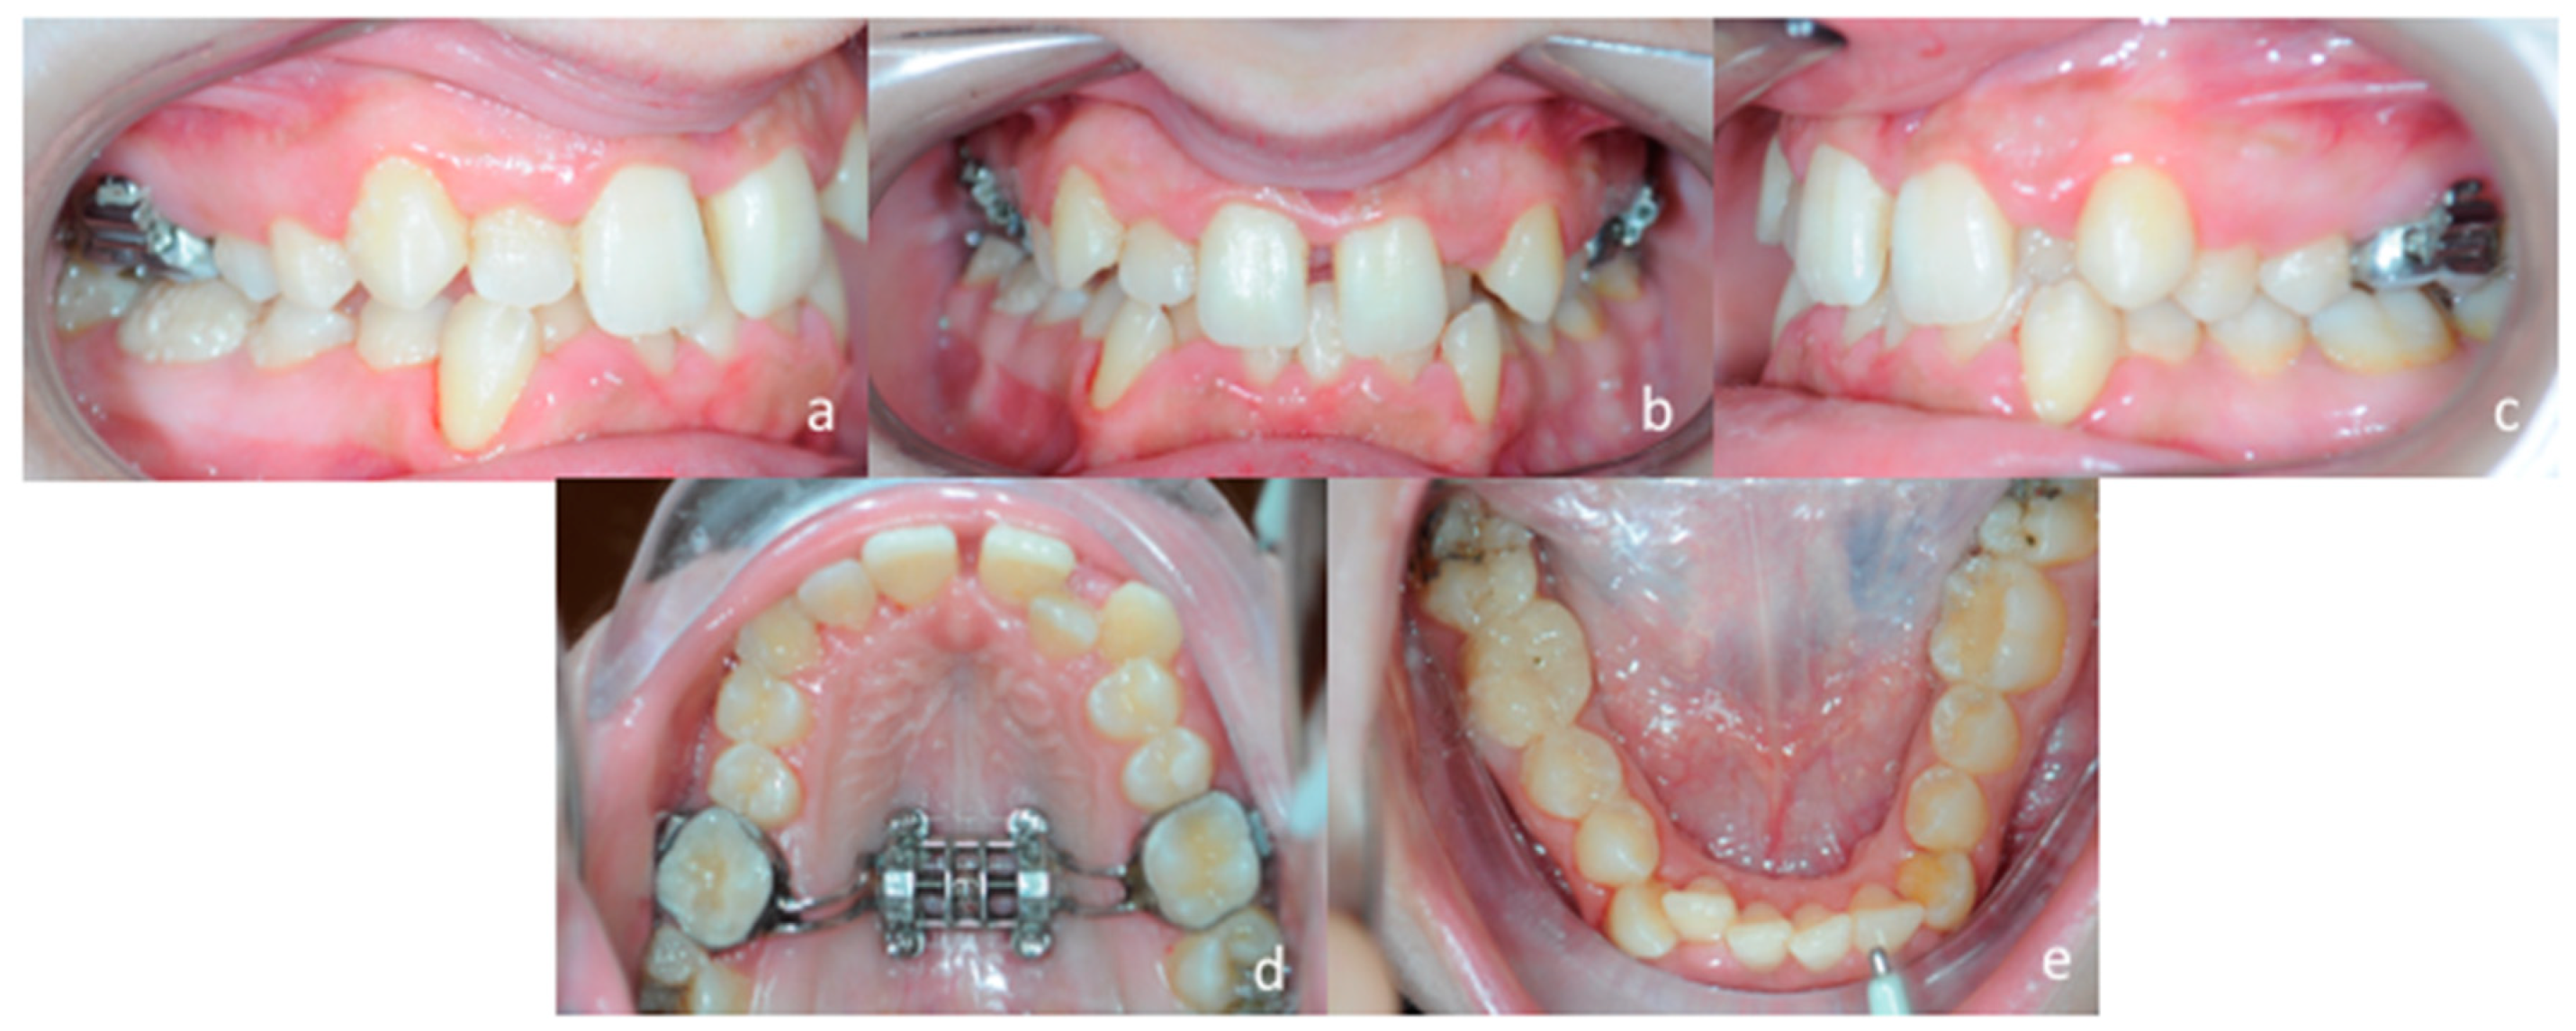

3.4. Treatment Progress

Evaluation of the effectiveness of the skeletal maxillary expansion procedure was performed two weeks later. Intra-oral inspection showed resolution of the posterior cross-bite at the right side and the appearance of the diastema between maxillary central incisors, which confirmed a skeletal opening of the midpalatal suture (Figure 12a–e). Then, activations were interrupted, and the MSE expander was locked. The patient was seen every month to monitor the retention phase of palatal expansion before bonding fixed orthodontic appliances.

Figure 12.

Post expansion intra-oral examination. (a) right lateral occlusion, (b) front view, (c) left lateral occlusion, (d) occlusal view of the maxillary arch, (e) occlusal view of the mandibular arch.